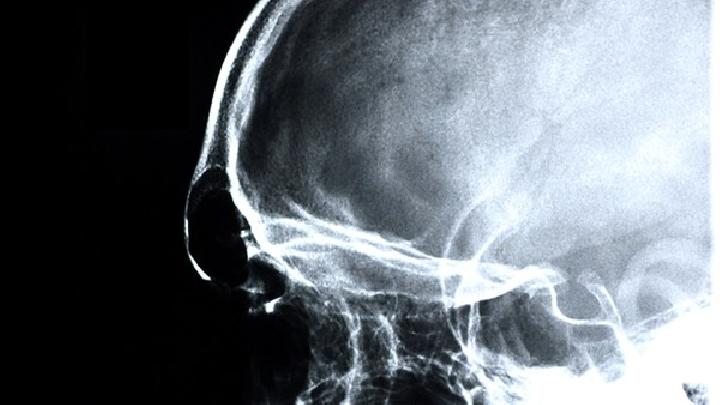

散发性脑炎是脑部疾病中常见的一种。在生活中,许多人可能不太了解这种疾病。在疾病发生的早期阶段,它可能很难检测到,也很容易延误疾病。今天,为了让您对散发性脑炎有一定的了解。小编详细解释了散发性脑炎的症状。感兴趣的朋友不妨一起看看。